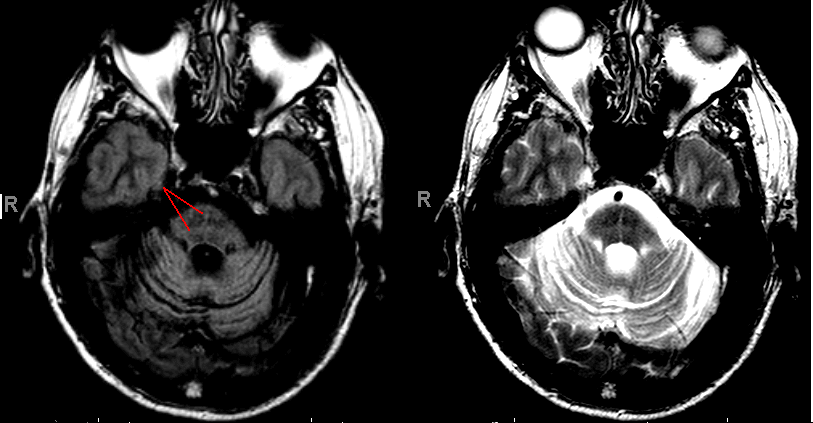

MSA hot cross buns sign

One radiographic sign that is helpfu in diagnosing MSA is a “hot-crossed buns” appearance in the pons. Thought to be due to selective loss of ponto-cerebellar fibers, the sign consists of T2 hyperintensity that divides the pons into quadrants. The example shown below is from a patient with MSA-C (red lines point to the abnormal hyperintensities crossing the pons).